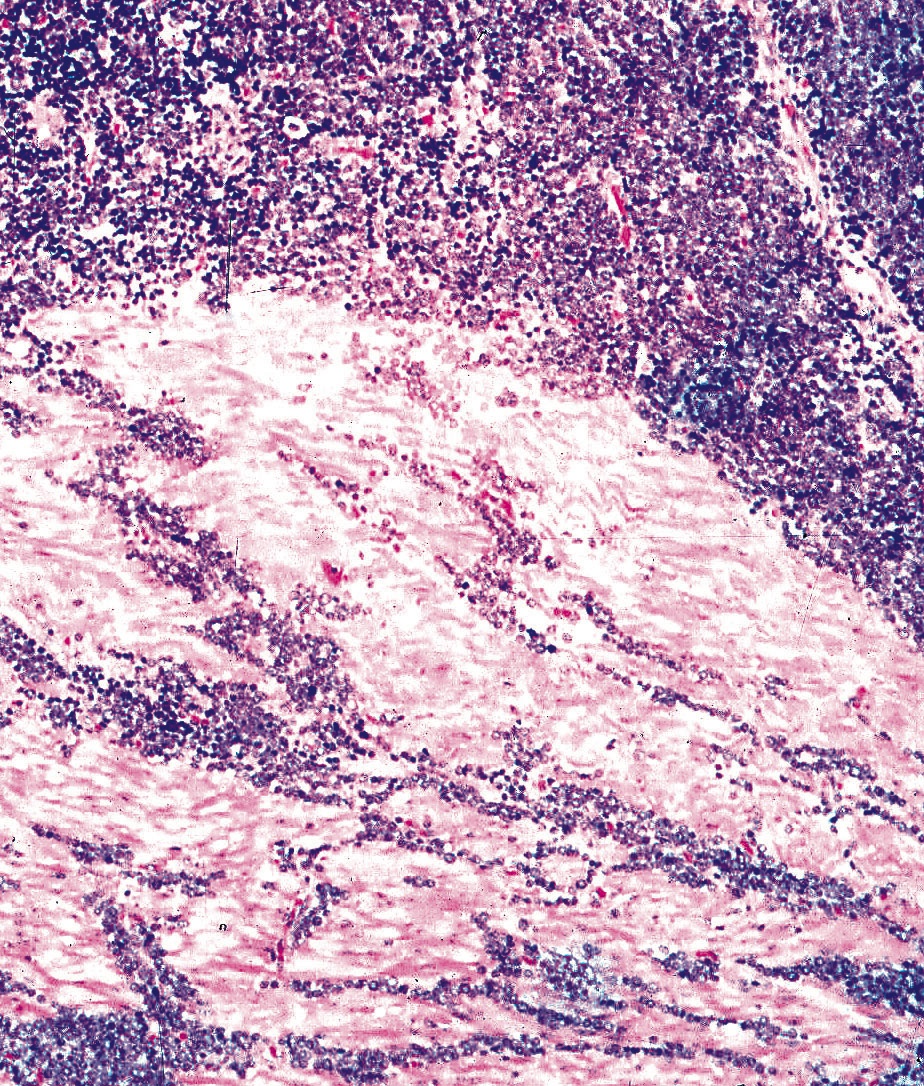

From www.researchgate.net

Immunohistochemical pictures of neuroendocrine carcinoma of esophagus Neuroendocrine Cancer Esophagus neuroendocrine carcinomas (necs) of the esophagus are extremely rare and poorly understood. the clinicopathological features and optimum treatment of esophageal neuroendocrine carcinoma. in total, 39 esophageal net were analyzed and 38 were neuroendocrine carcinoma (nec). to collect the cells, the doctor might insert a long, thin tube with a light and a camera on the end. Neuroendocrine Cancer Esophagus.

Histology of well and poorly differentiated aggressive neuroendocrine Neuroendocrine Cancer Esophagus the clinicopathological features and optimum treatment of esophageal neuroendocrine carcinoma. to collect the cells, the doctor might insert a long, thin tube with a light and a camera on the end into your lungs. esophageal neuroendocrine tumors (nets) are rare, aggressive and lacking specific symptoms. neuroendocrine carcinomas (necs) of the esophagus are extremely rare and poorly. Neuroendocrine Cancer Esophagus.

Esophageal biopsy showing highgrade neuroendocrine carcinoma Neuroendocrine Cancer Esophagus neuroendocrine carcinomas (necs) of the esophagus are extremely rare and poorly understood. esophageal neuroendocrine tumors (nets) are rare, aggressive and lacking specific symptoms. the clinicopathological features and optimum treatment of esophageal neuroendocrine carcinoma. to collect the cells, the doctor might insert a long, thin tube with a light and a camera on the end into your. Neuroendocrine Cancer Esophagus.